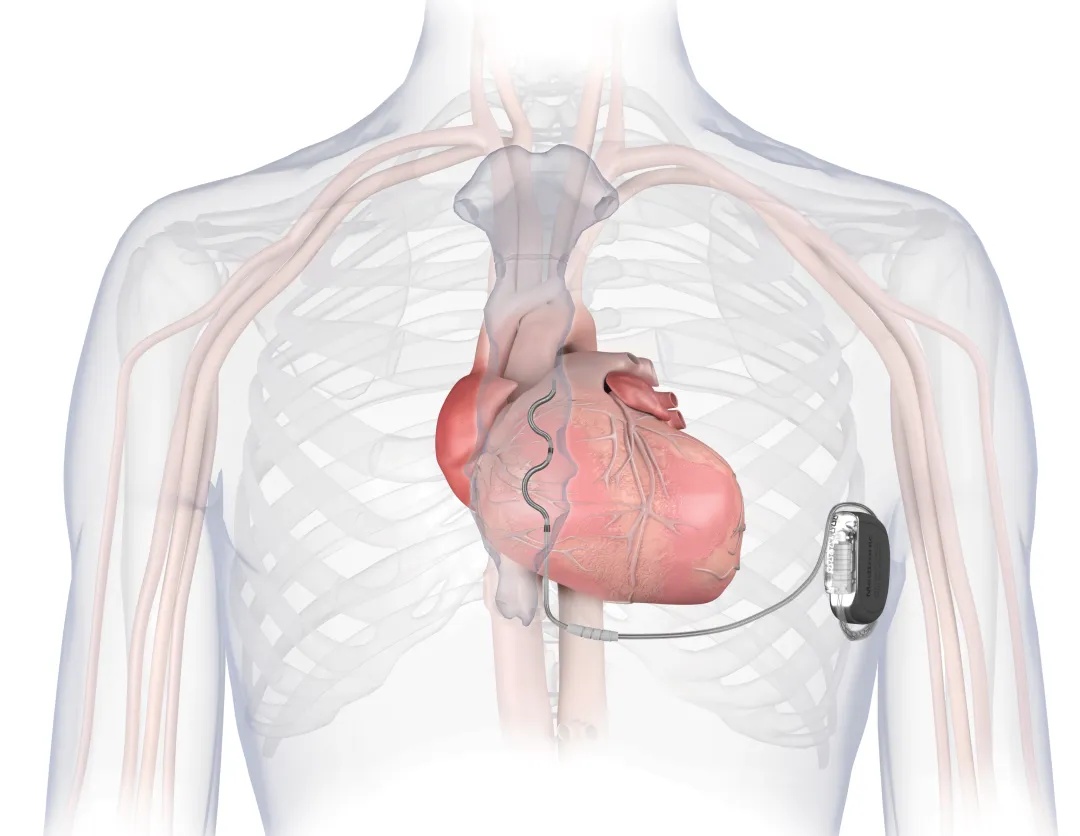

正在两难之际,曲新凯主任团队带来了一个新选择——Aurora EV-ICD™血管外植入式除颤器。这种新型设备无需将电极放入心脏或血管,而是通过微创手术,将电极放置在胸骨下的特定位置,同样能实现全天候监测和自动除颤功能。患者和家人听后,当即决定选择这项新技术。

本次植入的Aurora EV-ICD™于2025年6月刚获批入市,是全球最新的植入式除颤系统。它与传统技术相比,主要有以下优势:

路径更优,损伤更小:电极无需植入心脏和血管内,避免了对心脏和血管的潜在损伤,降低了相关并发症风险。

功能齐全,治疗高效:不仅能够除颤,还能进行抗心动过速起搏治疗,有效处理多种危险心律。

寿命长久,经济减负:预估使用寿命可达11.7年,减少了患者未来因电池耗竭而更换设备的次数和医疗负担。

生活影响小:装置体积小,植入后外观更不明显,且兼容全身核磁共振检查,对患者日常活动、运动康复及后续可能需要的影像学检查限制更少。